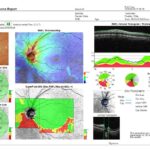

SUPERB OCT TECHNOLOGY READY FOR DELEGATION

An easy-to-use and completely automated OCT with color fundus photography to provide comprehensive glaucoma and retinal pathologies analysis

WIDE FIELD OCT SCAN

The 12mm x 9mm wide field OCT scan for the optic nerve and macula provides a fast screening and clear overview in a single image.